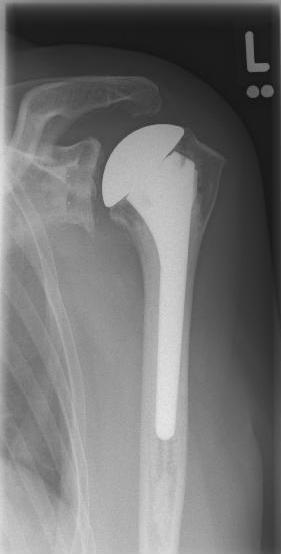

Conventional stem prostheses for omarthrosis and acetabular wear

right: anatomical shoulder prosthesis with glenoid replacement (Affinis type, Mathys company)

Short stem prostheses as modern implants for omarthrosis and acetabular wear

left: X-ray image of a short-shaft prosthesis

right: Short-shaft prosthesis (Affinis Short type, Mathys company)